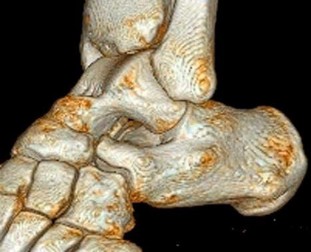

A 30-year-old female sustains a midfoot injury after falling from a horse. Radiographs demonstrate diastasis between the bases of the 1st and 2nd metatarsals. In a normal anatomic state, the native Lisfranc ligament originates and inserts on which two bony structures?

Correct Answer: Lateral aspect of the medial cuneiform to the medial aspect of the base of the 2nd metatarsal

Explanation:

The Lisfranc ligament is a stout, obliquely oriented intra-articular ligament that acts as the primary stabilizer of the second tarsometatarsal joint complex. It connects the lateral aspect of the medial cuneiform to the medial aspect of the base of the second metatarsal. Importantly, there is no direct ligamentous connection between the bases of the first and second metatarsals.